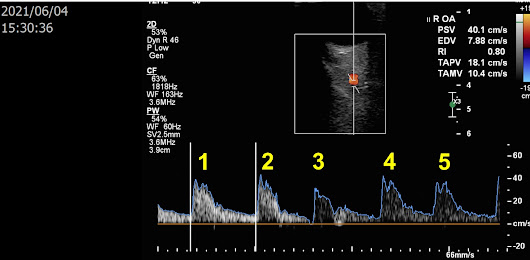

這是一位 87 歲的爺爺,大範圍腦中風,昨天下午在做腦血管超音波時過世,最後的影像告訴了我們重要的生理現象: 腦是人體的總指揮,就算在心跳停止之前仍然持續運作、眼睛是靈魂之窗,也是到最後一刻血流都維持正常。

圖一. 下午三點 30 分 36 秒時,右眼眼動脈流速仍正常,心搏數一個畫面仍有五次

圖二. 下午三點 31 分 08 秒,左眼眼動脈流速亦正常,心搏數開始降為一個畫面四次,另可見爺爺有心律不整的狀況 (長期的心房顫動),每一個心搏的間隔不一。

圖三. 下午三點 36 分 11 秒,基底動脈流速仍正常,但心搏數再降為一個畫面兩次

圖四. 下午三點 36 分 42 秒,心搏的間隔拉長了,顯示心搏又變慢了

再下一張即找不到顱內的動脈血流,病人心跳停止、臉色變得蒼白,因年齡太大且中風三十年,家屬放棄急救,爺爺平靜往生。